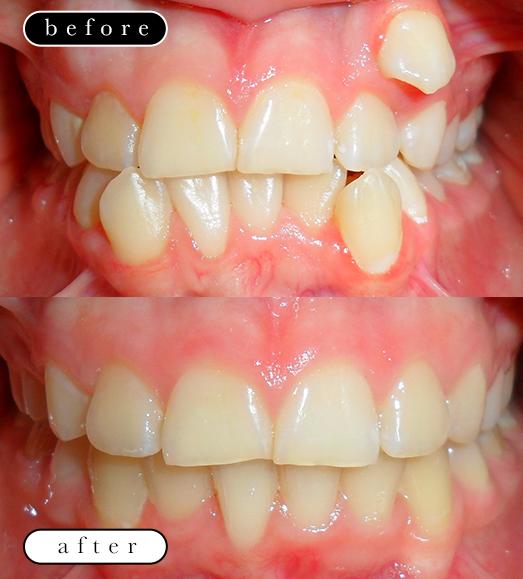

O našoj kvaliteti najbolje govore naši rezultati!